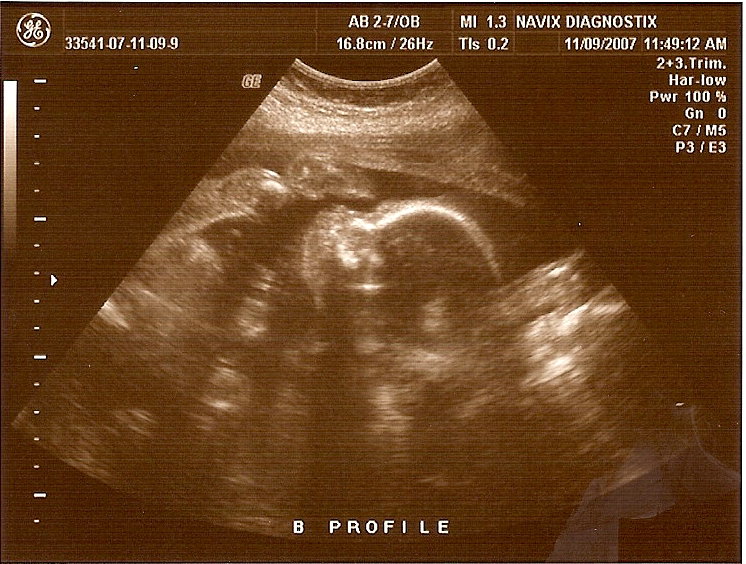

In Boston they put her on medication to arrest her contractions since she was steamrolling into labor, eventually they finally subsided late that night. The next morning she was well enough to be moved down to a different floor where they keep the mother's to be on bedrest. She was much more comfortable in that room and was feeling better. She continued to feel better on the 26th and was taken off her IV's and was able to take a shower. Here are some pics of the belly, and mom after she felt a little more human.